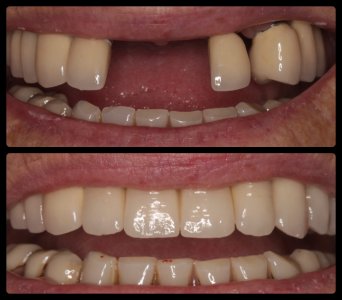

ΠΕΡΙΣΤΑΤΙΚΑ ΜΕ ΤΟΠΟΘΕΤΗΣΗ ΕΝΔΟΟΣΤΙΚΩΝ ΕΜΦΥΤΕΥΜΑΤΩΝ. ΌΠΟΥ ΧΡΕΙΑΣΤΗΚΕ ΠΡΑΓΜΑΤΟΠΟΙΗΘΗΚΕ ΑΝΑΠΛΑΣΗ ΟΣΤΟΥ ΚΑΙ ΟΥΛΙΚΩΝ ΕΛΕΙΜΜΑΤΩΝ ΜΕ ΧΡΗΣΗ ΜΟΣΧΕΥΜΑΤΩΝ ΚΑΙ PRF